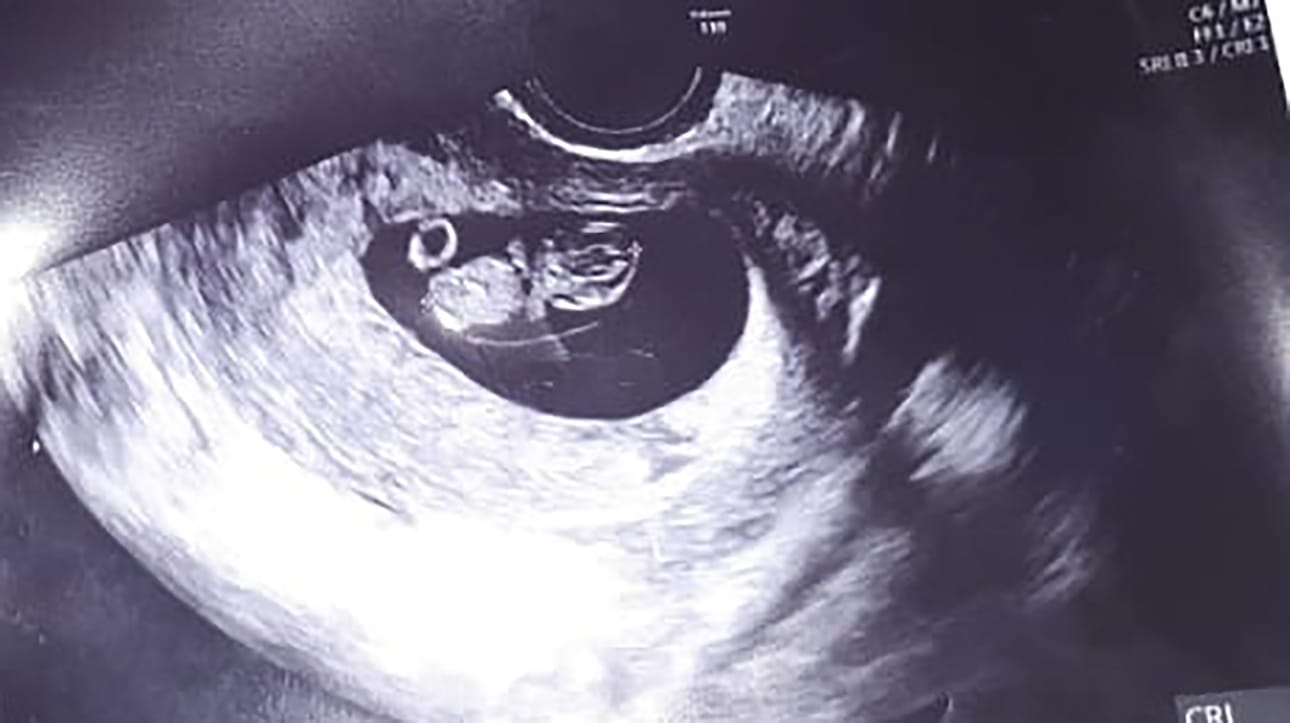

Kauan odotettu Lavin syntyi 24 vuoden hartaan odottamisen jälkeen. Erittäin vaikean raskausajan kokenut Jasmin-äiti muistuttaa: Ihmeitä voi tapahtua!